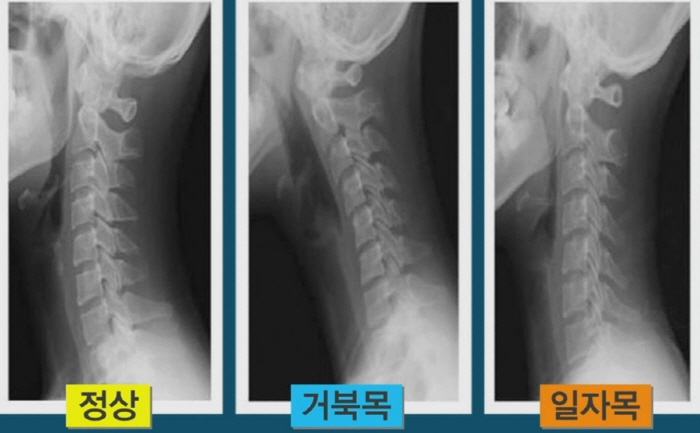

다만 40대 미만인 사람의 목 통증은 근육 긴장과 함께, 일자목·거북목일 가능성이 높습니다.

일자목·거북목은 당장 목디스크와 큰 관련은 없지만, 10~20년 후에는 병이 될 수 있습니다.

정상적인 목은 C자 커브를 이뤄야 정상인데, 목이 일자가 되면 디스크로 가는 압력이 증가하기 때문에

장기적으로 병으로 발전할 가능성이 있습니다.